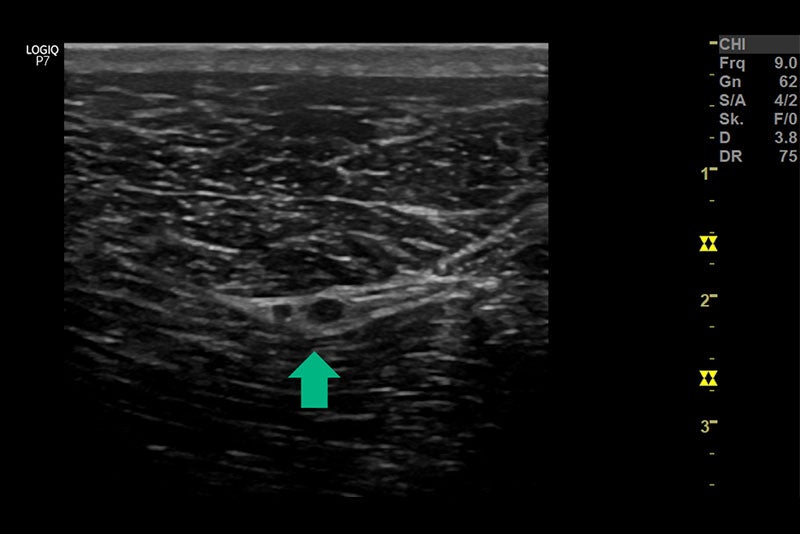

Tibial and common peroneal nerve in sheath of connective tissue (arrow)

Injectie onder ultrasone controle in het perineurale bindweefsel